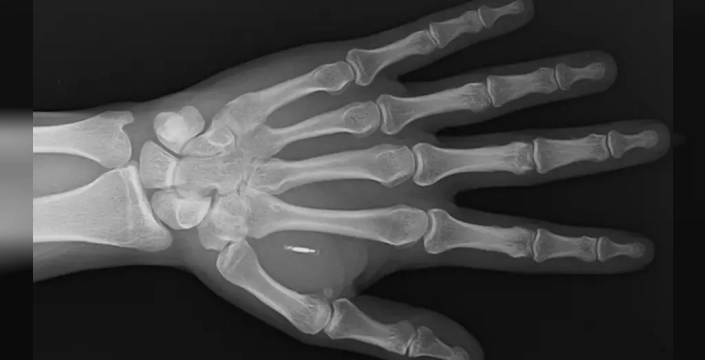

ABD'nin Missouri eyaletinde yaşayan Zi Teng Wang, eline yerleştirdiği mikroçipin şifresini unuttu. Sihirbaz ve moleküler biyolog olan Wang, eğlenceli bir fikirle eline mikroçip implantı yerleştirirken beklenmedik bir durumla karşılaştı.

Wang, Facebook'ta yaşadığı durumu paylaşarak, başparmağı ile işaret parmağı arasındaki etin içinde görünen mikroçipin röntgen görüntüsünü de gösterdi. Wang,